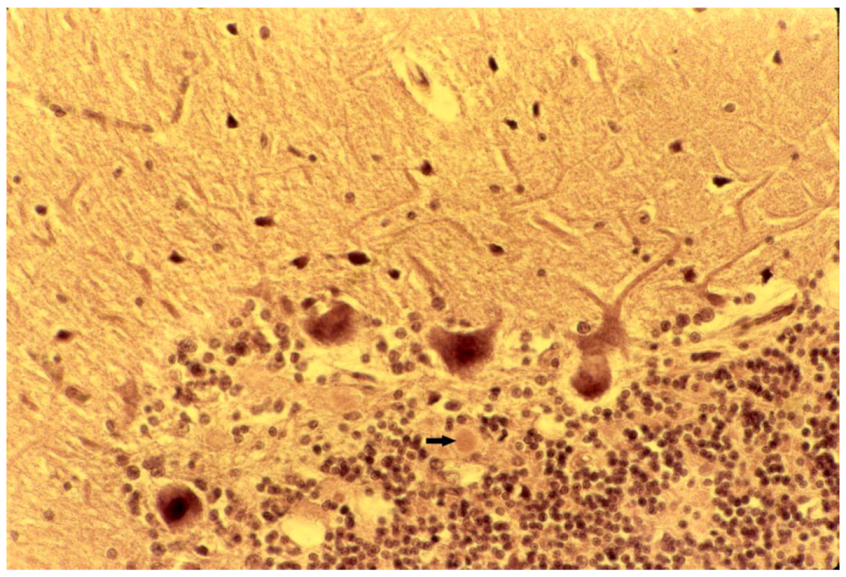

8. Neuropathology